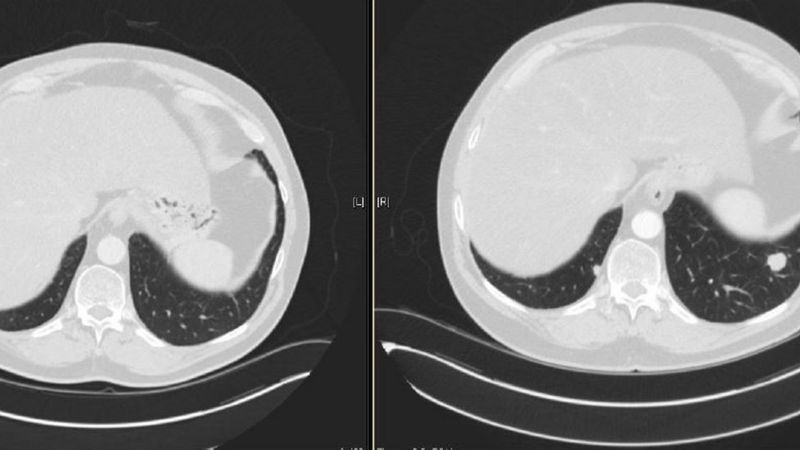

Lung Screenings Save Lives

Lung Screenings Save Lives medicine.yale.edu

screening